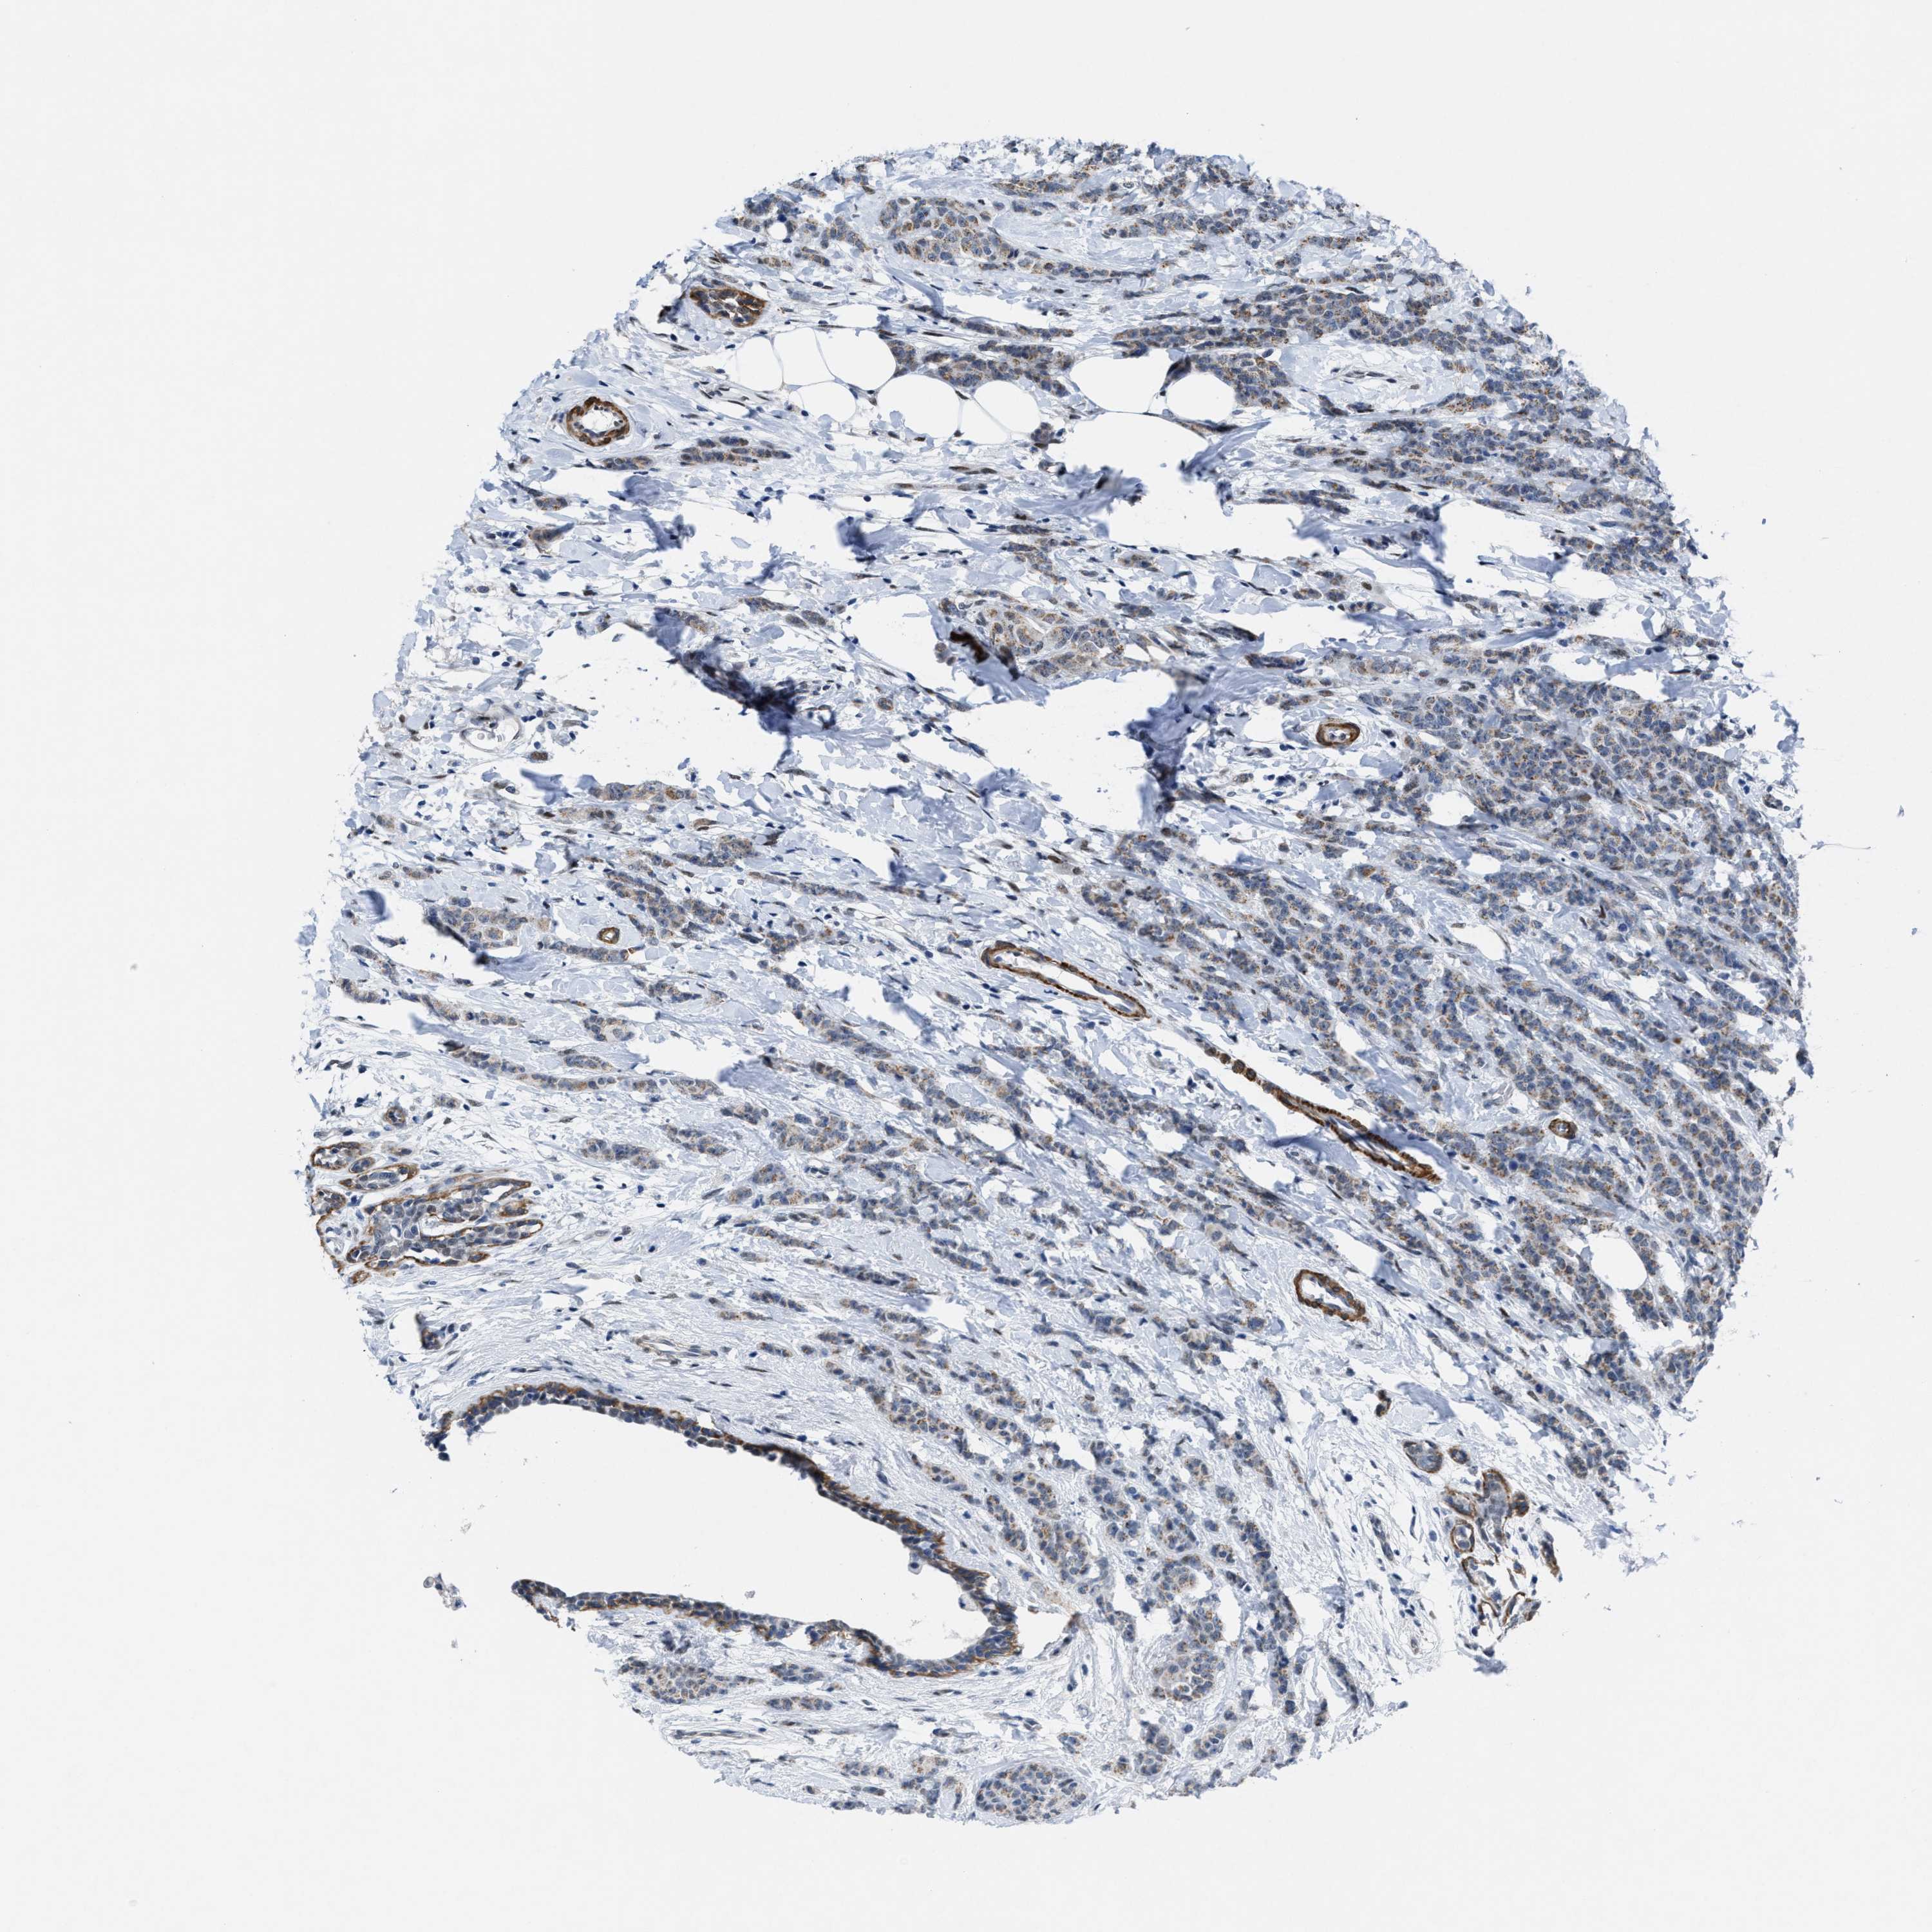

CANCER BREAST CANCER Show tissue menu

BRCA TCGA BRCA VALIDATION PROTEIN EXPRESSION

ANTIBODIES

AND

VALIDATION